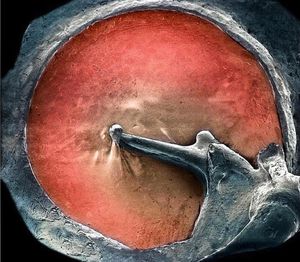

You haven't seen your EARDRUM as detailed as that before! And it looks awesome :) Coloured scanning electron micrograph (SEM) of an eardrum (red). The eardrum, or tympanic membrane, is located in the middle ear. It joins the inner ear through three tiny bones called the ossicles (malleus, incus and stapes). The malleus (centre) is attached to the inner eardrum. It articulates with the incus (right), which, in turn, links to the stapes (not seen). The middle ear transforms sound into vibrations in the fluid of the inner ear, which are then sent as nerve signals to the brain. This procedure enables you to process the sonic waves of whatever hits your ear and therefore recognize voices, noise or music. 📸•Medicogram•